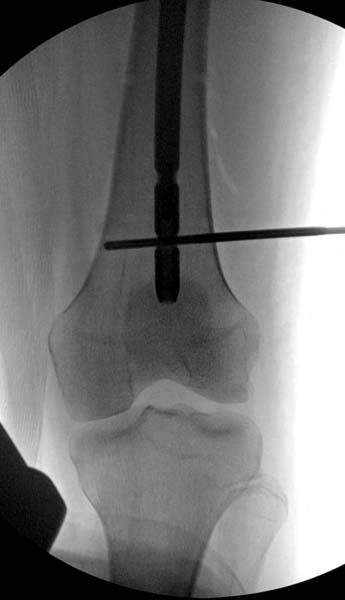

Больная стабильная после хирургических мероприятии и получив добро, приступили к закрытому вправлению таранной кости с укладкой наружного фиксатора. Затем укладка больную на бок и открытый остеосинтез перелома-вывиха головки бедра.

По характеру повреждения головка находится сзади и напрашивается задний Кохер-Лангенбек доступ, но в заднем доступе имеется риск повреждения магистрального кровоснабжения головки a. circumflexa. Более щадящая trochanteric flip (digastric osteotomy) сохранит кровоснабжение и дасть возможность работу при вывихнутом суставе.

Около 11.00 вечера больная переведена в реанимацию, без сознания, но стабильная.. На третьий день провели стабилизацию перелома бедра антеградным остеосинтезом.